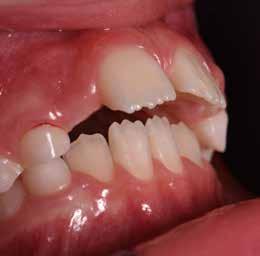

Presentazione del caso > F.V, bambino di cinque anni, presenta una malocclusione di II Classe scheletrica, III Classe dentale molare e canina destra e sinistra, morso inverso anteriore. Le arcate dentali mostrano usura degli elementi dentari anteriori a causa dell’occlusione patologica. Le linee mediane, superiore ed inferiore, sono centrate; il frenulo labiale superiore patologico per un’eccessiva estensione inter-incisale.

Dall’esame clinico si evince la III Classe dentale, l’inversione anteriore e l’over-jet negativo.

Considerazioni > L’analisi cefalometrica ad inizio trattamento dimostra la II Classe scheletrica con protrusione del mascellare superiore e prognazia mandibolare; tendenza alla crescita verticale. L’esame clinico evidenzia una protrusione mandibolare funzionale.